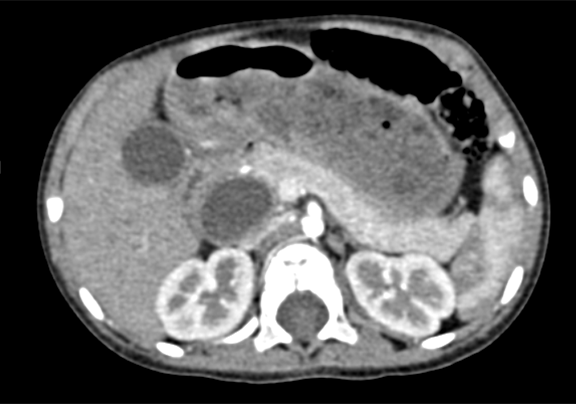

上腹部增强CT:符合先天性胆管扩张(胆总管)。

将0.625mm双源薄层CT资料的静脉期和动脉期Dicom格式文件导入海信CAS系统。

通过调节窗宽窗位调整CT序号,对肝实质,胆囊,胆总管,下腔静脉,肝动脉、门静脉及肝静脉等进行三维重建;系统自动计算肝脏体积。

术前CT检查:

动脉期

静脉期

平衡期